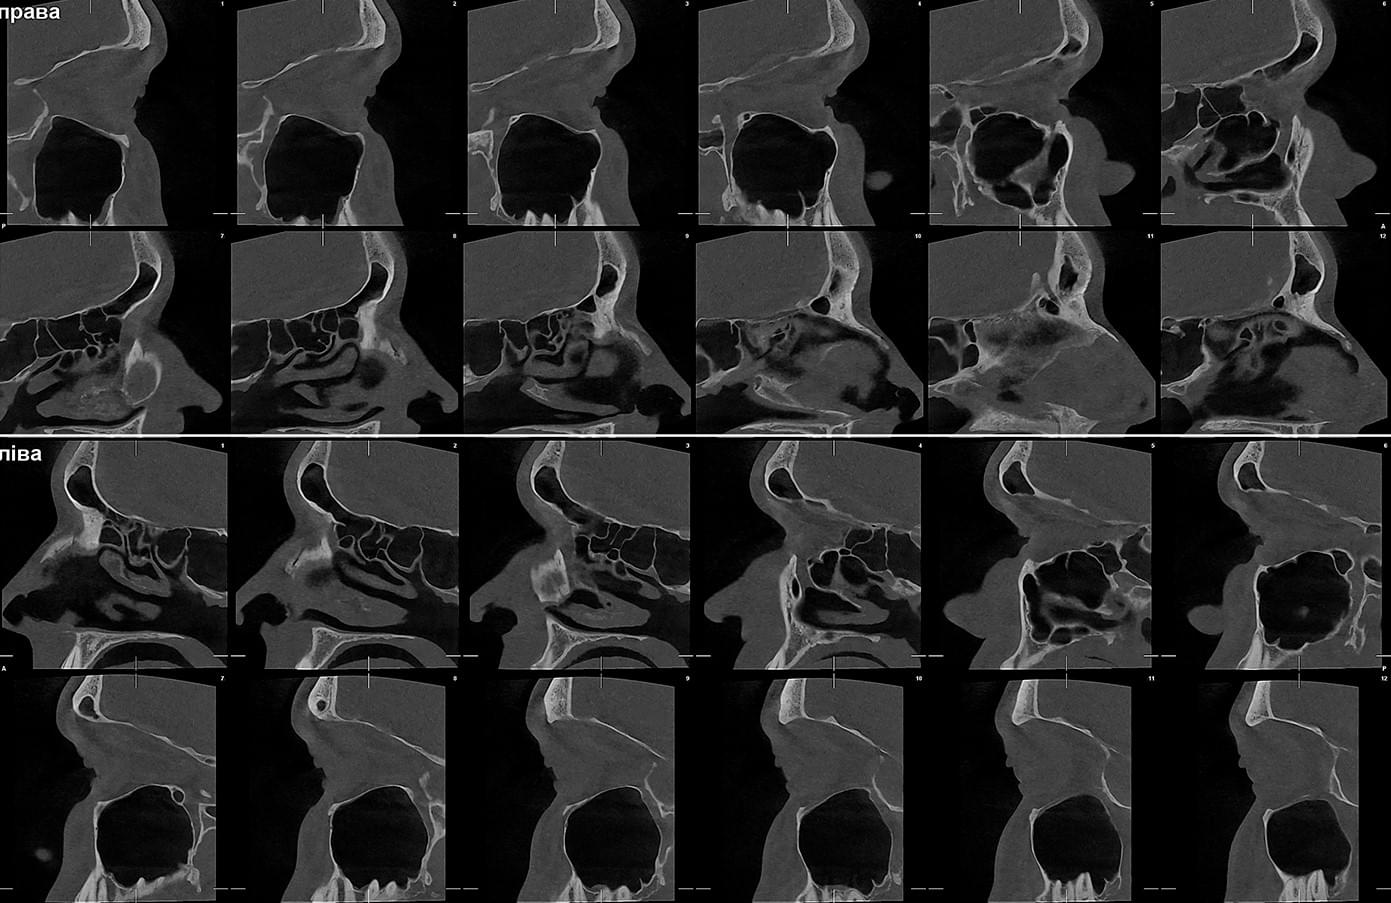

Діагностика гайморових пазух за допомогою КТ

У сучасній медицині КТ придаткових пазух носа (або КТ синусів) — це «золотий стандарт»

діагностики для ЛОР-лікарів та щелепно-лицевих хірургів. Звичайний рентген часто не

показує повну картину, а МРТ не завжди доступний і дорожчий. Комп’ютерна томографія дає

детальну 3D-модель усіх пазух (гайморових, лобних, клиновидних та решітчастого

лабіринту) за 10 секунд і з мінімальною дозою опромінення.

КПКТ (конусно-променева комп’ютерна томографія) — це 3D-знімок високої роздільної здатності. На відміну від звичайного рентгену, КТ показує: